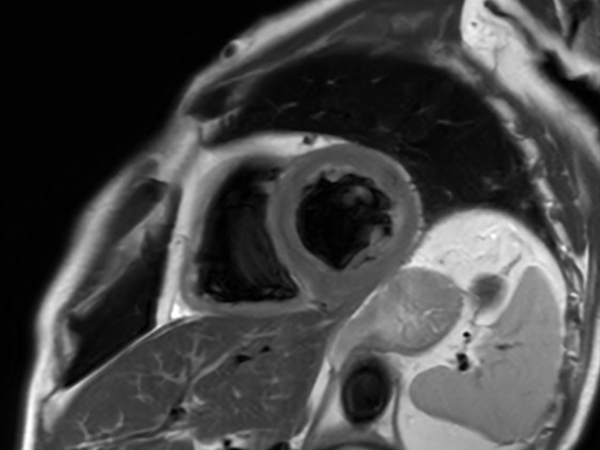

Comprehensive Cardiac with SmartSpeed Precise